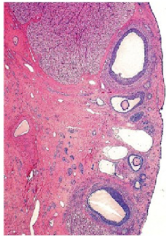

What organ is in the image provided and what phase of the estrous cycle is it in?

ovary in proestrus